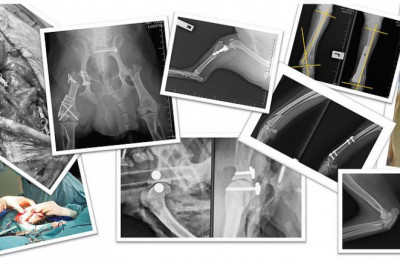

For Veterinarians | Pet orthopedic treatment Singapore

We provides pet orthopedic treatment singapore. Our caring and professional team are intensively trained to provide the best veterinary care for your pet.